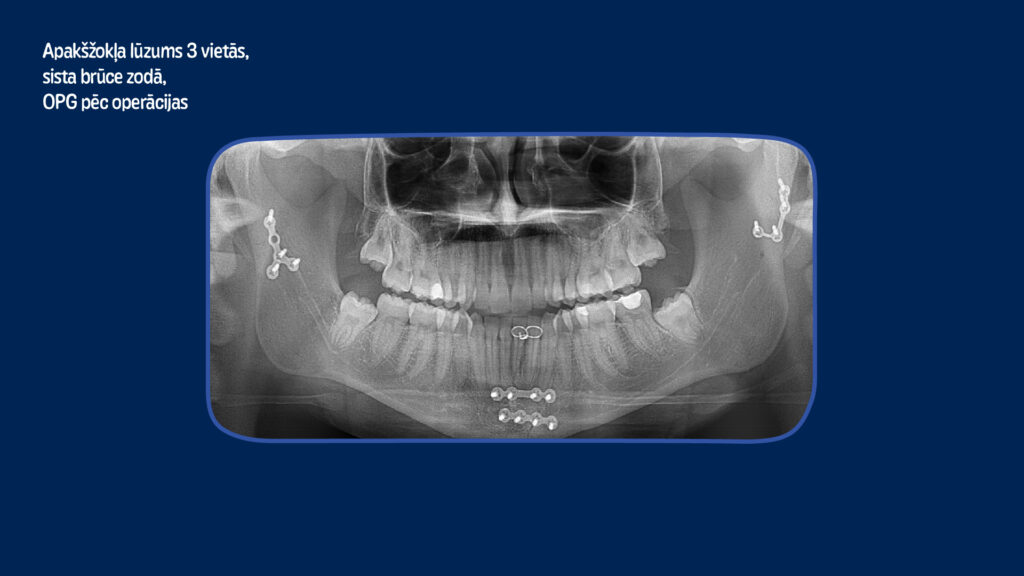

No 2021. līdz 2023. gadam kopumā Stradiņa slimnīcā ar dažādām galvas un sejas traumām pēc elektroskrejriteņu negadījumiem ārstējās 410 cilvēki, no kuriem 220 gadījumos tika konstatētas vaļējas galvas brūces, 71 gadījumā – apakšžokļa lūzums, 58 – vaiga kaula un augšžokļa lūzums, bet 46 gadījumos cietušajiem bija lauzti deguna kauli, liecina Stradiņa slimnīcas NMC Sejas un žokļu ķirurģijas traumpunkta ārsta palīga Edgara Freimaņa apkopotie dati.

“Sejas kaulu lūzumiem tiek veikta osteosintēze jeb kaulu savienošana ar metāla mini vai mikroplāksnēm, kas visbiežāk cilvēka organismā paliek uz mūžu. Osteosintēzes operācijas materiālu izmaksas ir 3000 līdz 5000 eiro, kas tiek segtas no valsts budžeta. Taču sejas traumas visbiežāk iekļauj arī zobu traumas, kuru ārstēšana pacientam jāsedz pašam no savas kabatas. Šādu traumu ārstēšana slimnīcā var ilgt līdz trīs nedēļām, bet visbiežāk pēc tam pacienti vēl līdz pat gadam turpina ārstēties ambulatori un zobārstniecības klīnikās,” stāsta A. Ivanova.